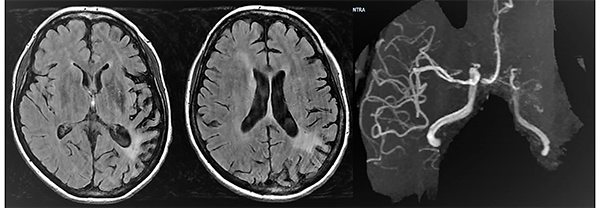

Caso clínico # 2: LD femenino de 51 años con antecedente de tabaquismo e hipertensión arterial, estudiada por deterioro cognitivo de varios meses de evolución. La RMN y ARM evidencia atrofia de hemisferio cerebral izquierdo con hiperintensidad periventricular y disminución franca del calibre de las arterias cerebral anterior y media izquierda con desarrollo de los vasos de MM (Fig. 3). La ADC muestra el stop de la arteria carótida interna izquierda distal y ausencia del origen de las cerebrales anterior y media, buen desarrollo de los vasos de MM y aporte de vasos meníngeos y etmoidales correspondiente a un grado 4 de Suzuki (Fig. 4). Se realizó una revascularización cerebral combinada: un bpTS izquierdo más EDMS y, para aumentar la perfusión en territorio de ambas arterias cerebrales anteriores, un EGPS bifrontal. En la TAC postoperatoria se evidenció un infarto fronto-polar mesial sin repercusión clínica. La ADC postoperatoria diferida evidencia una buena revascularización en los territorios de las arterias cerebral anterior y media a partir del bpTS y la doble sinangiosis (Fig. 5).

Fig. 3 Caso clínico # 2. RMN y ARM preoperatoria, se evidencia atrofia de hemisferio cerebral izquierdo con hiperintensidad periventricular y disminución franca del calibre de las arterias cerebral anterior y media izquierda con desarrollo de los vasos de MM